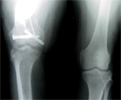

Malunion femur with Knee osteoarthritis in a 54 years old female Chinese

Pre

Op

Open comminuted fracture femur treeated with debridement and external fixator